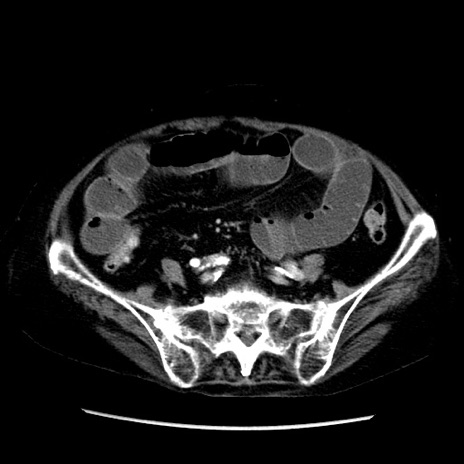

症例14(横断像)

【症例】 90歳代女性

【主訴】 腹痛・嘔吐

【現病歴】今朝から左側腹部痛を認めた。 経過観察していたが、嘔吐を認めたため来院。

【既往歴】 子宮癌術後

【身体所見】 意識清明、BP 127/54mmHg、P 98bpm Sp02 95%(RA)、BT 35.8°C、腹部平坦・軟腸ぜん動音聴取良好、右下腹部圧痛(+) 反跳痛なし

【データ】WBC 9800、CRP 0.46